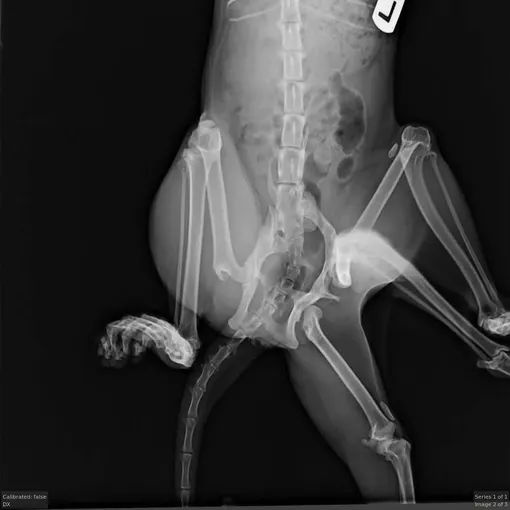

Кошка, которую позже назвали Битси, была доставлена в Центр спасения животных Forget Me Not Animal Rescue в Эдмонтоне, Альберта, в апреле 2025 года. После обследования спасательная команда обнаружила, что из спины Битси торчат две дополнительные конечности, и в общей сложности у нее шесть лап.

Ветеринары считают, что лапы у Битси появились от близнеца, которого она поглотила в утробе матери. К сожалению, три из ее лап были нефункциональными, что причиняло Битси дискомфорт и ограничивало ее подвижность.

Ветеринары из ветеринарной больницы Уиндермира в течение двух часов оперировали Битси. «Дополнительные конечности были прикреплены к одной из ее задних лап с помощью дополнительной части таза, которая также не была "живой", поэтому нам пришлось ампутировать две дополнительные конечности и заднюю ногу, чтобы обеспечить наилучшее качество жизни Битси», — сказал Маккензи Савацки, новый хозяин кошки.